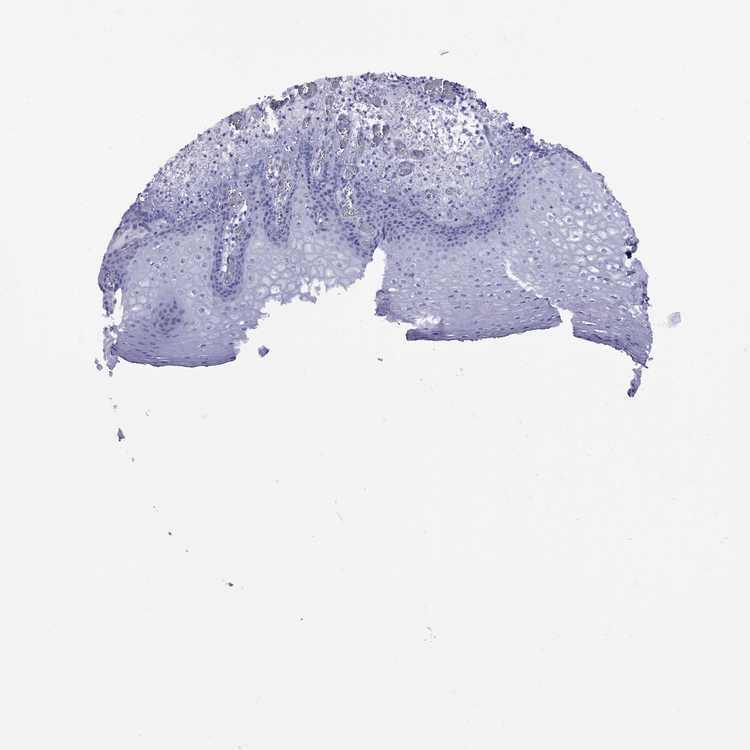

ESOPHAGUS - Antibody stainingi

Antibody staining in the annotated cell types in the current human tissue is reported as not detected, low, medium, or high, based on conventional immunohistochemistry profiling in selected tissues. This score is based on the combination of the staining intensity and fraction of stained cells.

Each image is clickable and will lead to virtual microscopy that enables deeper exploration of all samples and also displays staining intensity scores, fraction scores and subcellular localization as well as patient and tissue information for each sample.

Antibody HPA067335

Squamous epithelial cells Not detected